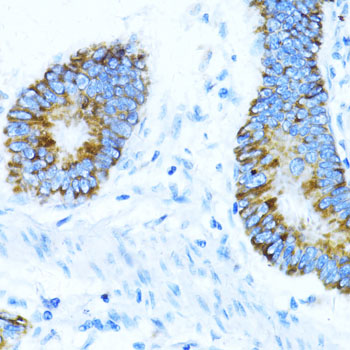

Immunohistochemistry of paraffin-embedded human colon carcinoma using NOX1 antibody. |